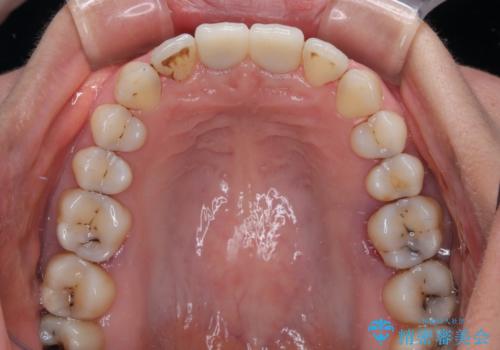

前歯の見た目はもちろん、出血や腫脹のない健全な前歯の状態を獲得することができました。